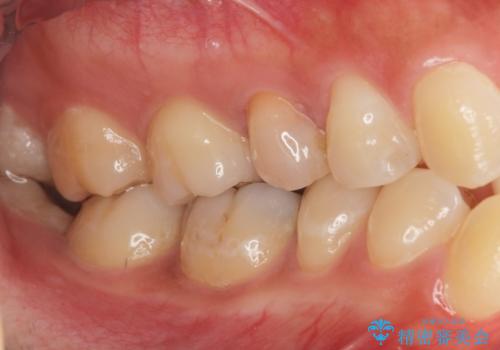

- 右上の5番目の歯の神経の治療のやり直しとセラミック治療を行いました。

術前ですでに変色が始まっているのがわかります。

途中矯正治療を挟んでいるため、少し歯並びがかわっています。